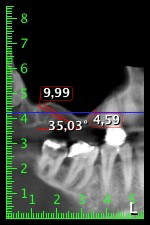

Para limitar el aumento a la región 14, se mantuvieron conversaciones con la paciente y se acordó una incorporación oblicua del implante 16 hacia la zona dorso-craneal (figura 8).

Este método permite exclusivamente una solución atornillada en la prótesis definitiva. Para que el puente pueda atornillarse en la zona oclusal, se necesita un pilar angulado (por ejemplo, a 35°) que permita el atornillado perpendicular a la zona de oclusión.

Imagen 8: Tomografía digital de volúmenes del ángulo de inserción para el implante 16.